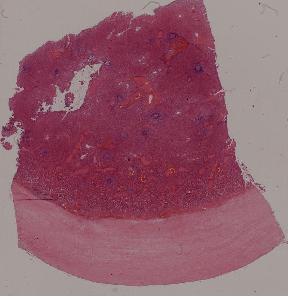

4.脾包膜玻璃样变